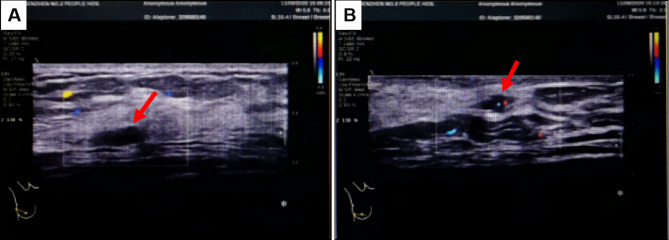

Case presentation: We report a unique case of APH in a 47-year-old female patient, which was 12 mm in diameter and characterized by tumor cell atypia. To date, six cases of APH have been reported in the literature, including the present case. The mean age of the APH patients was 49.5 years (range: 39-75 years). The majority of APHs (4/6) in the breast were initially diagnosed as angiosarcoma. The tumor in our study presented diagnostic challenges as an atypical APH due to its substantial size (12 mm), the presence of indistinct borders in certain regions, an extensive growth pattern, the hobnail appearance of endothelial cells, and the mitotic count.